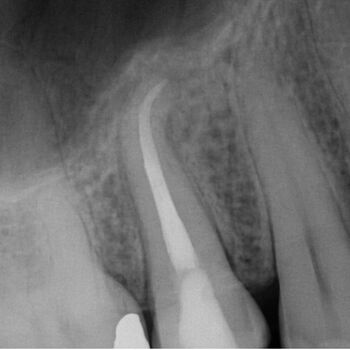

Fall 2: Entfernung eines Instrumentenfragmentes

Röntgenbild: Instrumentenfragment Ausgangssituation

Ausgangssituation